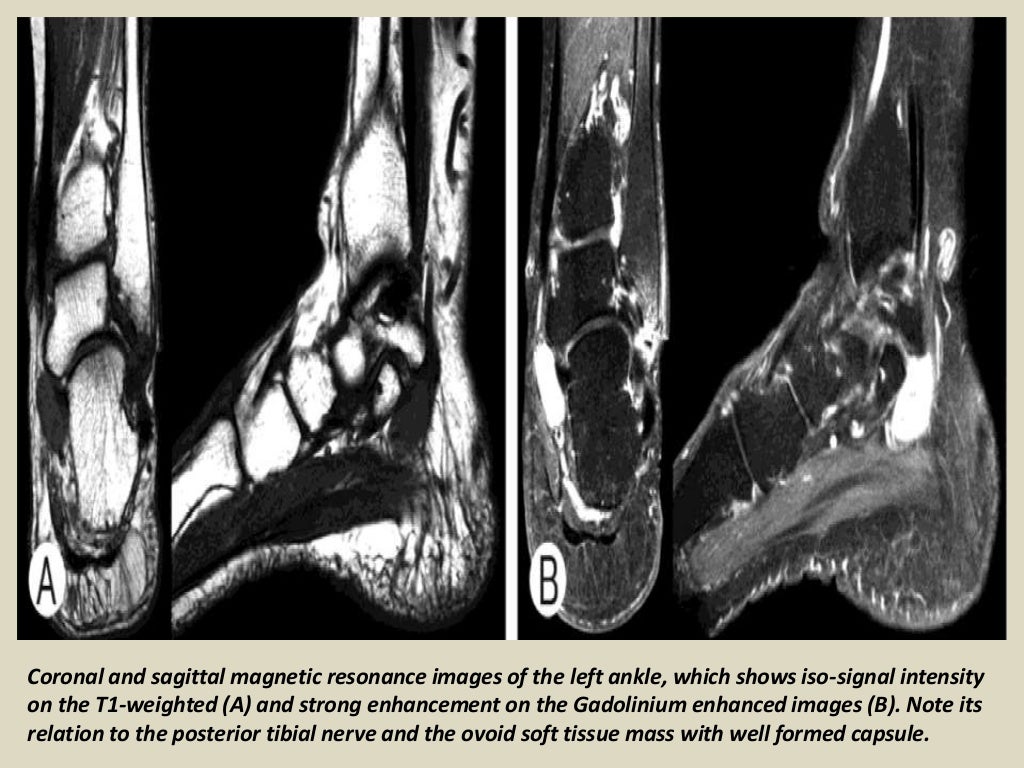

Presentation1 radiological imaging of tarsal tunnel syndrome.

Presentation1 radiological imaging of tarsal tunnel syndrome. Tarsal Tunnel Syndrome X Ray Tarsal tunnel syndrome refers to an entrapment neuropathy (tunnel syndrome) of the (posterior) tibial nerve or of its branches within the tarsal tunnel. Tarsal tunnel syndrome refers to an entrapment neuropathy (tunnel syndrome) of the (posterior) tibial nerve or of its branches within. Mr imaging can accurately depict the contents of the tarsal tunnel and the courses of the terminal. Tarsal Tunnel Syndrome X Ray.

Presentation1 radiological imaging of tarsal tunnel syndrome. Tarsal Tunnel Syndrome X Ray This condition is analogous to carpal tunnel. Tarsal tunnel syndrome is a compressive neuropathy of the tibial nerve at the level of the tarsal tunnel which can lead to pain. Tarsal tunnel syndrome (tts) is a common entrapment syndrome whose diagnosis can be difficult. Tarsal tunnel syndrome refers to an entrapment neuropathy (tunnel syndrome) of the (posterior) tibial nerve or. Tarsal Tunnel Syndrome X Ray.

Presentation1 radiological imaging of tarsal tunnel syndrome. Tarsal Tunnel Syndrome X Ray This condition is analogous to carpal tunnel. Tarsal tunnel syndrome is a compressive neuropathy of the tibial nerve at the level of the tarsal tunnel which can lead to pain. Tarsal tunnel syndrome refers to an entrapment neuropathy (tunnel syndrome) of the (posterior) tibial nerve or of its branches within the tarsal tunnel. Tarsal tunnel syndrome refers to an entrapment. Tarsal Tunnel Syndrome X Ray.